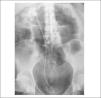

Cinco años después de iniciado el tratamiento con topiramato (dosis de 375 mg/día), la paciente acude a urgencias por presentar un cuadro de fiebre y dolor de tipo cólico en fosa renal derecha. Se le realiza un sedimento de orina en el que se observan más de 100 leucocitos/campo y abundantísimos gérmenes, y una radiografía simple de abdomen en la que se evidencia un cálculo coraliforme de 5,07 × 3,56 cm de diámetro en el riñón derecho y pequeños cálculos caliciales en riñón izquierdo (fig. 1). Posteriormente, este hallazgo se confirma mediante una urografía intravenosa, que además descarta la presencia de uropatía obstructiva y de reflujo vesicoureteral.